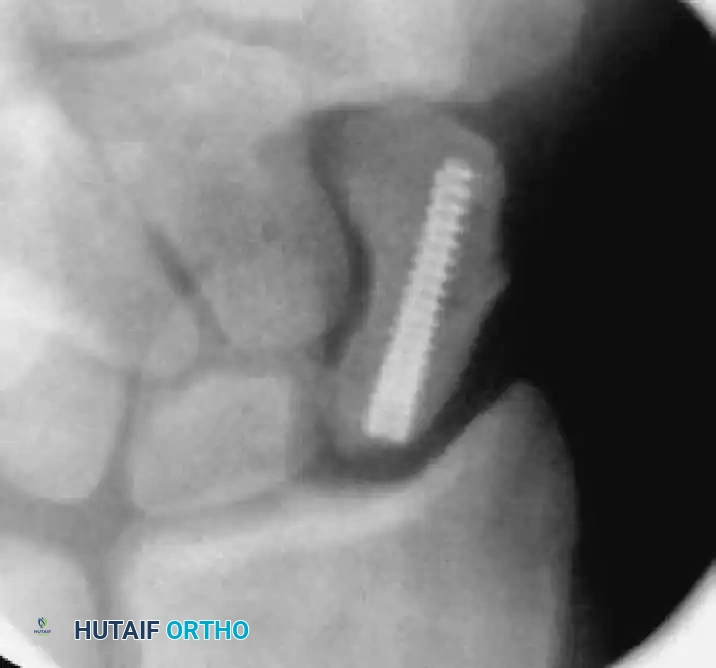

6. Screw Insertion and Countersinking

• Select the appropriate headless compression screw (e.g., Acutrak), ensuring it is 4 mm shorter than the measured scaphoid length.

• Advance the screw over the guidewire using the cannulated screwdriver.

• Monitor the insertion under fluoroscopy. The variable pitch of the headless screw will compress the fracture site as it is advanced.

• Drive the screw until the trailing edge is buried 1 to 2 mm beneath the proximal articular cartilage, and the leading edge is 1 to 2 mm short of the distal cortex.

Screw Insertion A

Screw Insertion B

Screw Insertion C

FIGURE: (A) Joysticks and anti-rotation wires are maintained during dorsal implantation of the screw. (B, C) Final fluoroscopy confirms the precise placement and countersinking of the headless compression screw.

• Remove the guidewire, anti-rotation wires, and joysticks. Obtain final multi-planar fluoroscopic images to verify fracture compression, anatomic reduction, and complete intraosseous screw containment.